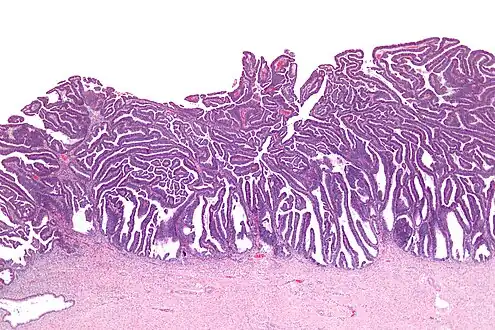

The name of the lesion describes it microscopic appearance. It has nipple-like structures with fibrovascular cores (papillae) that are long in relation to their width (villus-like), which are covered with a glandular pseudostratified columnar epithelium.

Micrograph of a villoglandular adenocarcinoma the cervix. H&E stain.

Very low magnification